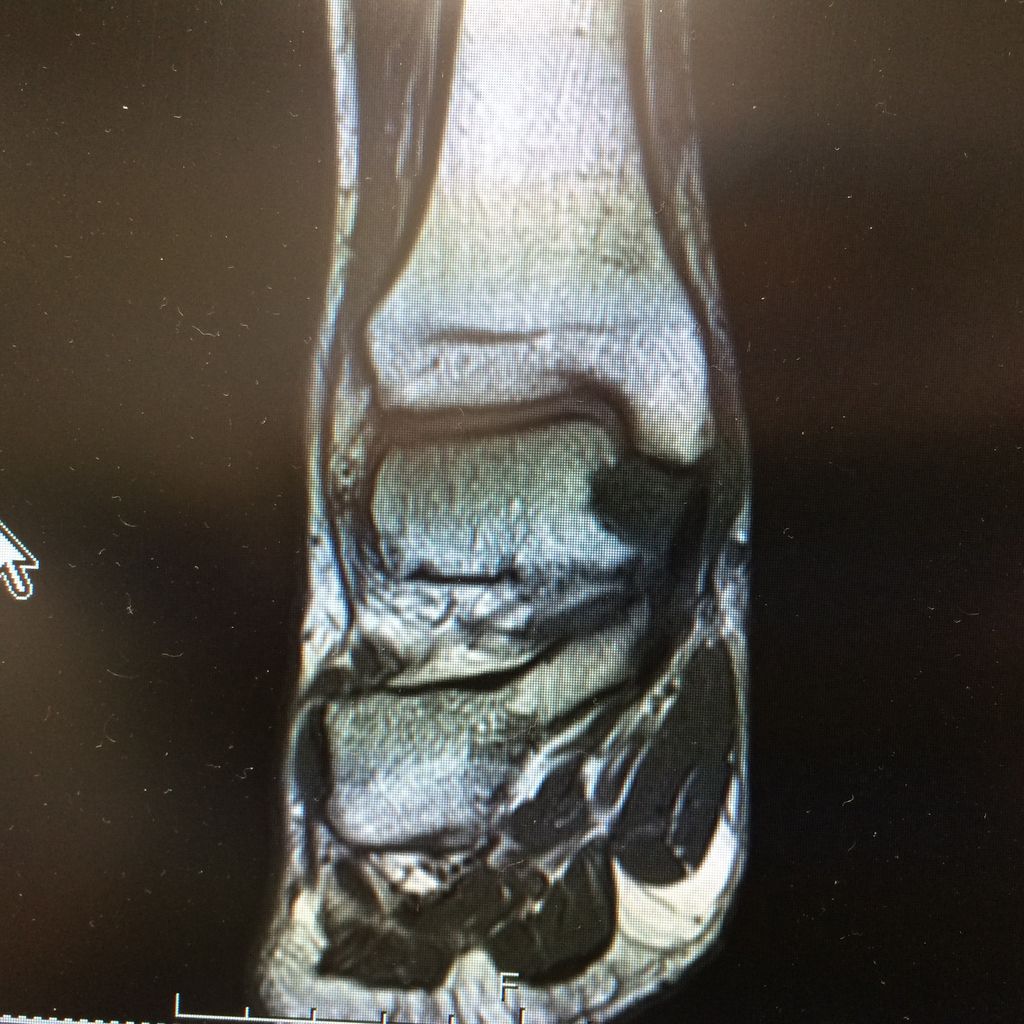

で、こういう画像が出来上がります。マウスの操作で360度、グリグリ動くのですが、詳しくは詳細を調べた来週——ということで、診察室を出たところで、先生がいきなりやってきてもう一度部屋に入るように促されました。

「この中心部分の少しくぼんでいることろが痛い部分と一致しますね」

「せ、先生、それは……」

「とりあえず一致するということで。ではまた来週!」